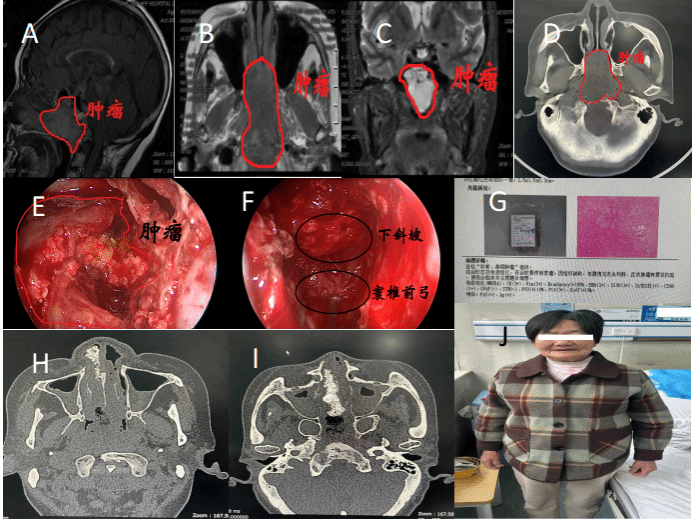

入院相关检查发现,肿瘤巨大,主体位于颅底,侵袭并破坏斜坡和蝶窦骨质,寰椎前弓等部骨质已悉数破坏,两侧紧邻基底动脉及双侧颈内动脉斜坡旁段,向后毗邻脑干;肿瘤前界已突入中鼻道和下鼻道,下界已突入口咽顶部。随着肿瘤的生长侵袭,有可能进一步向脑干及口咽方向侵袭,最终造成患者窒息、严重的神经功能障碍,甚至死亡。

图 A-D术前肿瘤影像结果;E内镜下切除蝶窦腔内肿瘤情况;F内镜下肿瘤切除后探查寰椎前弓及下斜坡等结构;G术后病理;H-I术后复查鼻窦CT;J患者术后恢复情况

为提高手术的成功率,降低术中风险,神经外科刘重霄教授团队在术前为患者制定了详尽的个体化手术方案。术中通过神经内镜角度调整,充分显露下斜坡段,尤其是脑干腹侧骨质侵袭破坏最为明显的环枢椎部;利用好肿瘤的假包膜标识,防止对颈内动脉斜坡旁段的损伤;尽可能保留带蒂的鼻中隔-鼻底粘膜瓣,减少可能致命的下斜坡段脑脊液漏;应用神经导航,在脑干腹侧部再次精准定位,防止对脑干的损伤;同时应用等离子刀在肿瘤非核心区切除,控制术中出血。手术当天,雷晓明教授、刘鸿涛主治医师负责全身麻醉,师蔚教授和周任教授现场指导,刘重霄教授主刀,郭振宇副主任医师和黄廷钦博士配合,在神经内镜下“抽丝剥茧”,顺利切除肿瘤。术中出血控制良好,约400ml;脑干腹侧硬膜未见明显脑脊液漏。患者术后恢复良好,未再诉头疼,于术后10天出院。